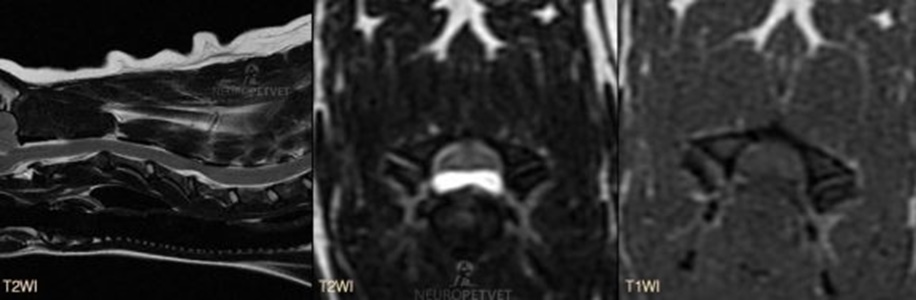

MRI από σκύλο με οξείας εμφάνιση τετραπάρεσης με αδυναμία βάδισης και αταξία λόγω HNPE στο επίπεδο των νευροτομίων Α4–Α5. Στην MRI απεικονίζονται τα τυπικά χαρακτηριστικά της HNPE που είναι: Η συμπίεση του νωτιαίου μυελού πάνω από μεσοσπονδύλιο δίσκο. Σε εγκάρσιες τομές, το υλικό συχνά παρουσιάζει δίλοβο περίγραμμα ή «σαν φτερά γλάρου» μορφή, η οποία θεωρείται χαρακτηριστική. Η εμφάνιση με δίλοβο περίγραμμα οφείλεται στην παρουσία του μηνιγγοσπονδυλικού συνδέσμου που χωρίζει το υλικό. Το υλικό εμφανίζεται συνήθως με ομοιογενή αύξηση σήματος στις Τ2 ακολουθίες, ενώ παραμένει με ίση ένταση σήματος στις Τ1 ακολουθίες. Ο σκύλος ανάρρωσε πλήρως μετά από κοιλιακή αποσυμπίεση (ventral slot) στο μεσοσπονδύλιο διάστημα Α4-Α5.